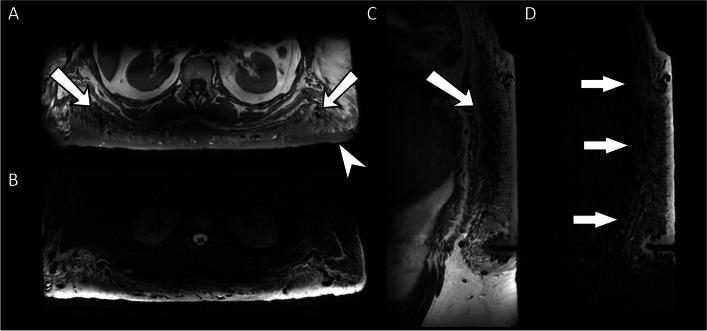

Somatic overgrowth disorders comprise a wide range of rare conditions that present with focal enlargement of one or more tissue types. The PI3K-AKT-mTOR pathway is a signalling pathway that induces angiogenesis and cell proliferation, and is one of the most commonly overactivated signalling pathways in cancer. The PI3K-AKT-mTOR pathway can be up-regulated by genetic variants that code for proteins in this pathway, or down-regulated by proteins that inhibit the pathway. Mosaic genetic variations can result in cells that proliferate excessively in specific anatomical locations. The PIK3CA-related overgrowth spectrum (PROS) disorders include CLOVES syndrome, macrodystrophia lipomatosa, and Klippel-Trenaunay syndrome among many. The neurofibromatosis type 1 (NF1) gene encodes neurofibromin which down-regulates the PI3K-AKT-mTOR pathway. Thousands of pathological variants in the NF1 gene have been described which can result in lower-than-normal levels of neurofibromin and therefore up-regulation of the PI3K-AKT-mTOR pathway promoting cellular overgrowth. Somatic overgrowth is a rare presentation in NF1 with a wide range of clinical and radiological presentations. Hypertrophy of all ectodermal and mesodermal elements has been described in NF1 including bone, muscle, fat, nerve, lymphatics, arteries and veins, and skin. The shared signalling pathway for cellular overgrowth means that these radiological appearances can overlap with other conditions in the PIK3CA-related overgrowth spectrum. The aim of this review is to describe the genetic basis for the radiological features of NF1 and in particular compare the appearances of the somatic overgrowth disorders in NF1 with other conditions in the PIK3CA-related overgrowth spectrum.